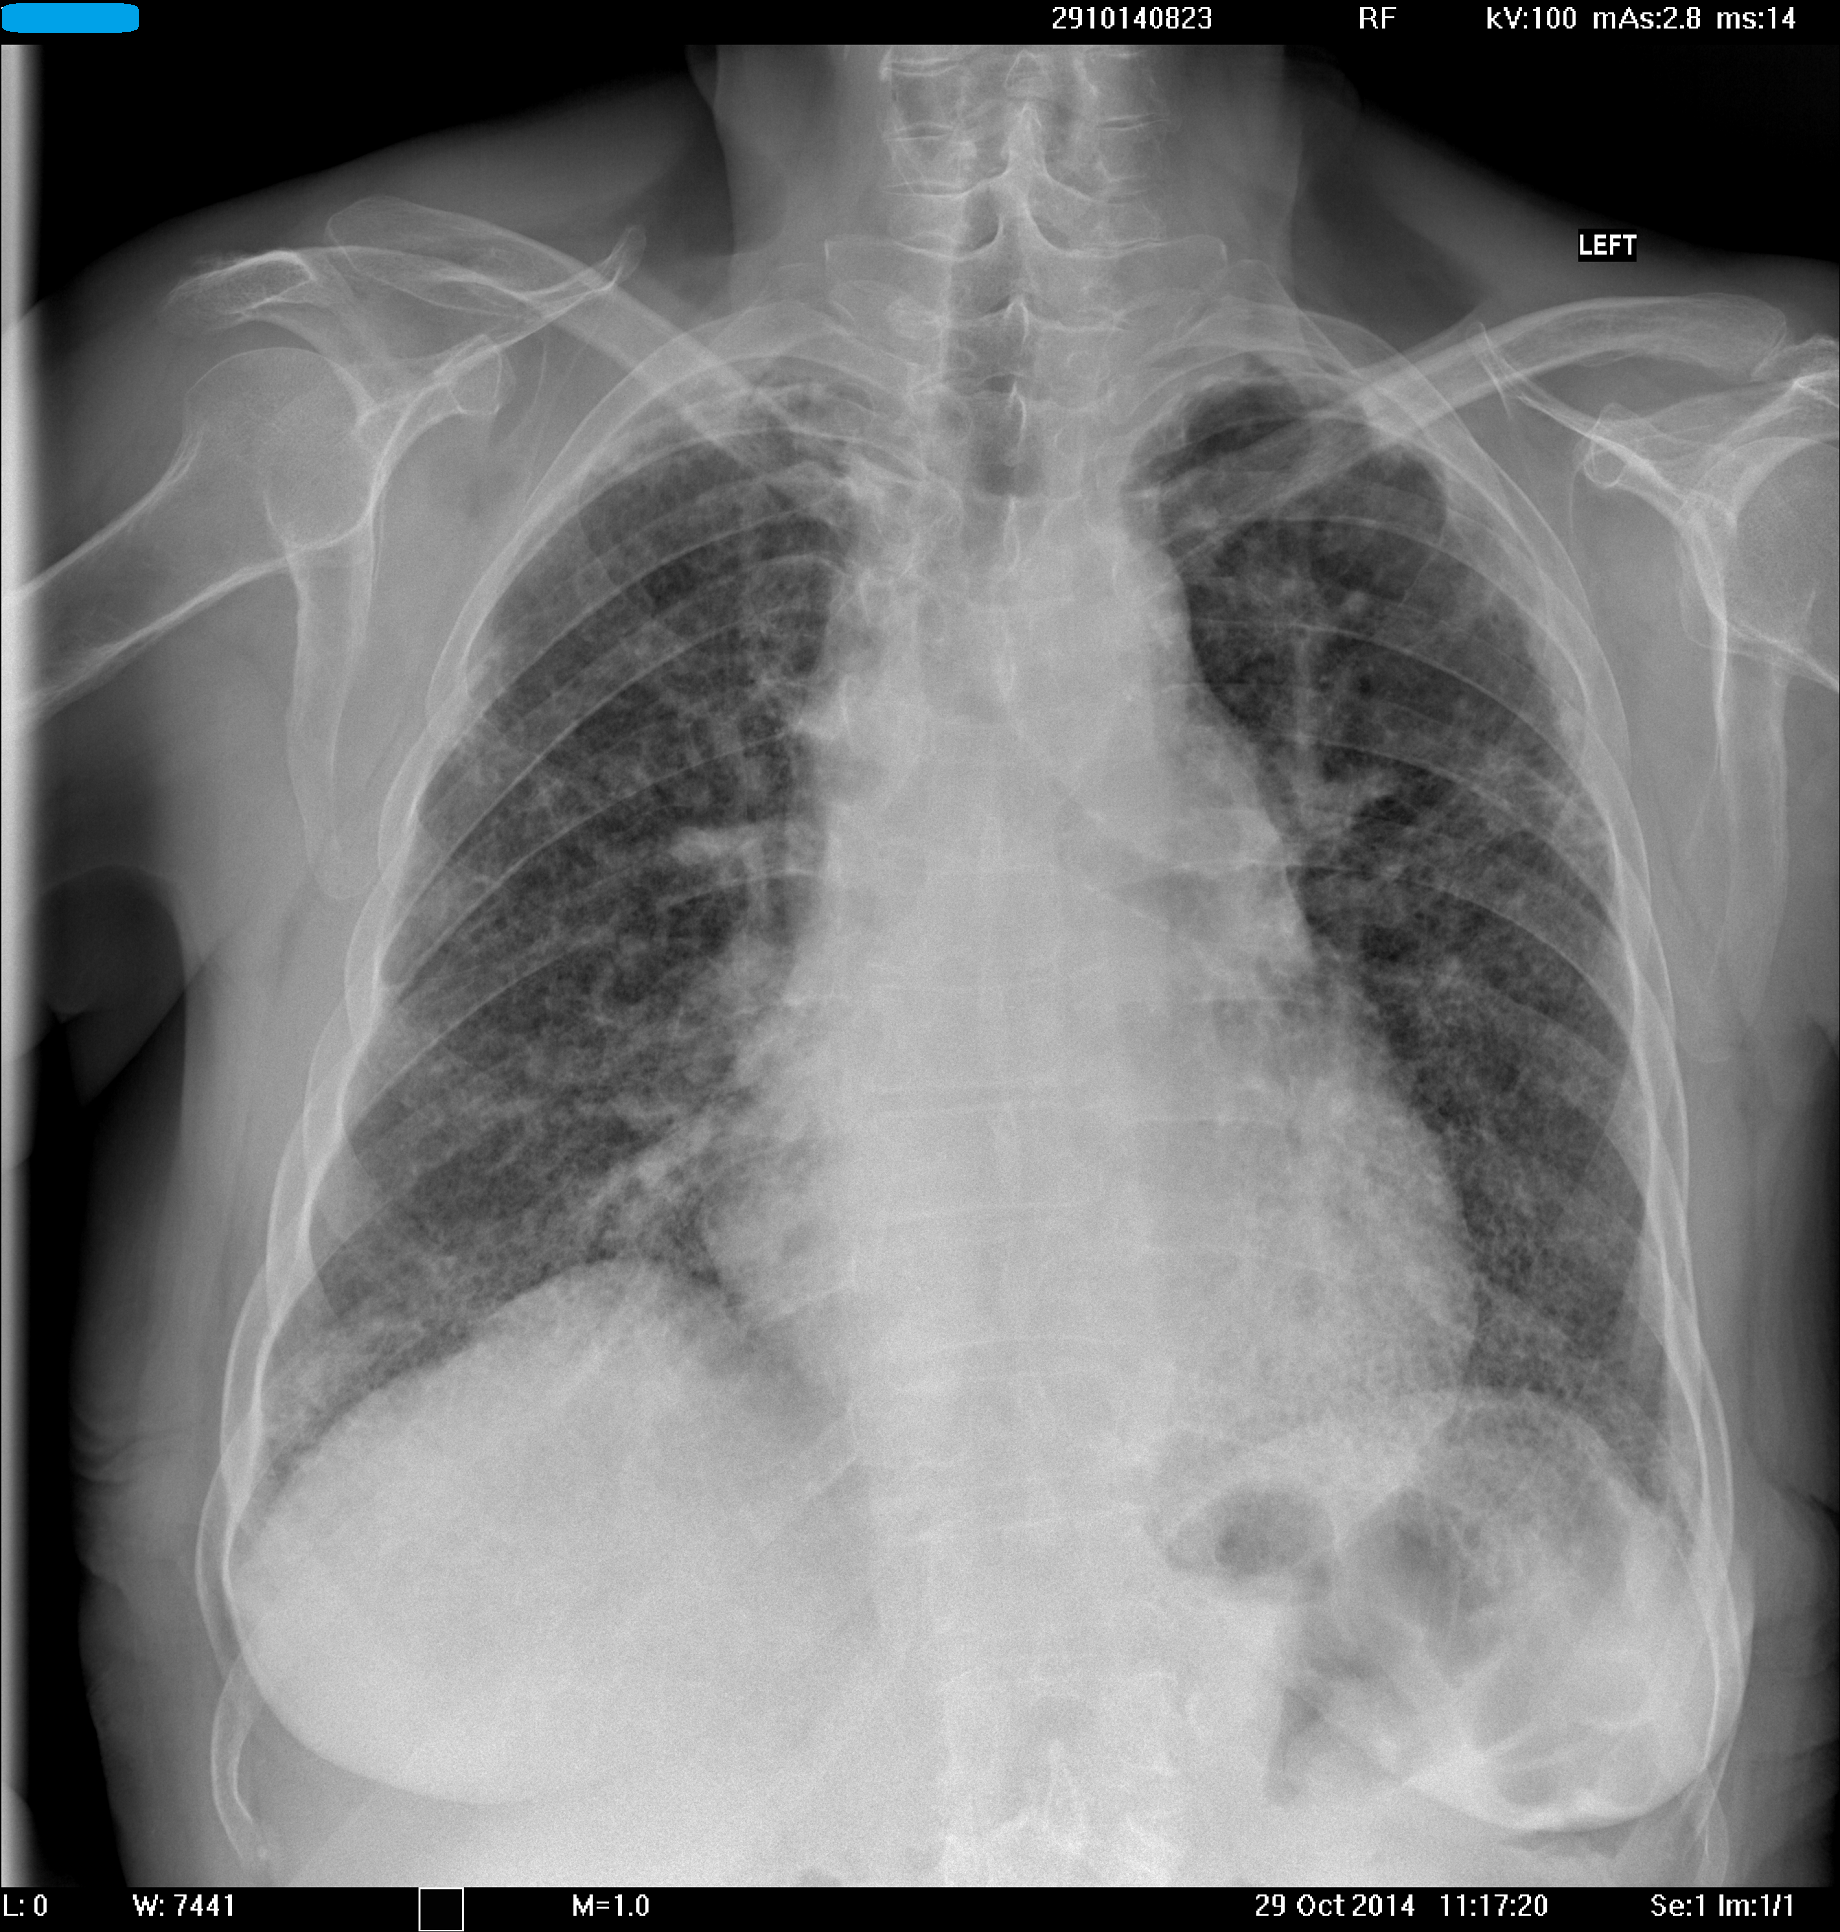

О, нет. Перчик не в строфантине.

Некий другой. Вызывающий представленные изменения в легких.

такие изменения могут быть из-за амиодарона. :roll:

Наконец-то!!! Браво!!! Долгожданная ЭВ-РИ-КА!!!!

Конечно, наш любимый надежный доказательный кордарон. Но черт возьми не такой уж и безопасный.

Кордароновый альвеолит!!!!